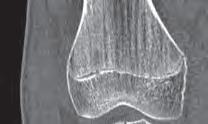

Rycina 17.81.

A, B – Genu recurvatum u pacjenta po złamaniu okolicy proksymalnej części chrząstki nasadowej piszczeli.

Rycina 17.82.

Uszkodzenie tętnicy podkolanowej wskutek złuszczenia nasady bliższej kości piszczelowej (S-H 1). Zagrożenie rozwojem zespołu przedziałów powięziowych jest poważne.

Rozpoznanie

Objawy złamania to silny ból uniemożliwiający stanie i chodzenie, zniekształcenie obrysów stawu kolanowego przez krwiak i różnego stopnia przemieszczenie nasady kości piszczelowej. Należy dokładnie zbadać stan ukrwienia i unaczynienia kończyny pod kątem objawów uszkodzenia tętnicy podkolanowej i nerwu strzałkowego. Trzeba ocenić bolesność uciskową oraz napięcie w przedziałach powięziowych podudzia: przednim, bocznym, tylnym powierzchownym i tylnym głębokim. U pacjentów z podejrzeniem wzmożonego ciśnienia wewnątrzprzedziałowego należy wielokrotnie powtarzać badanie ukrwienia i unerwienia kończyny, a w razie zaistnienia wskazań wykonać bezpośredni pomiar ciśnienia w przedziałach. Powinno się zawsze podejrzewać możliwość uszkodzeń więzadłowych współistniejących ze złamaniem. Badania obrazowe to RTG w pozycji AP, bocznej i skośnej. Wykonanie badania TK może być konieczne w celu pełnej oceny rozległości

złamania. W przypadku podejrzenia uszkodzenia tętnicy podkolanowej należy wykonać angio-TK lub arteriografię.